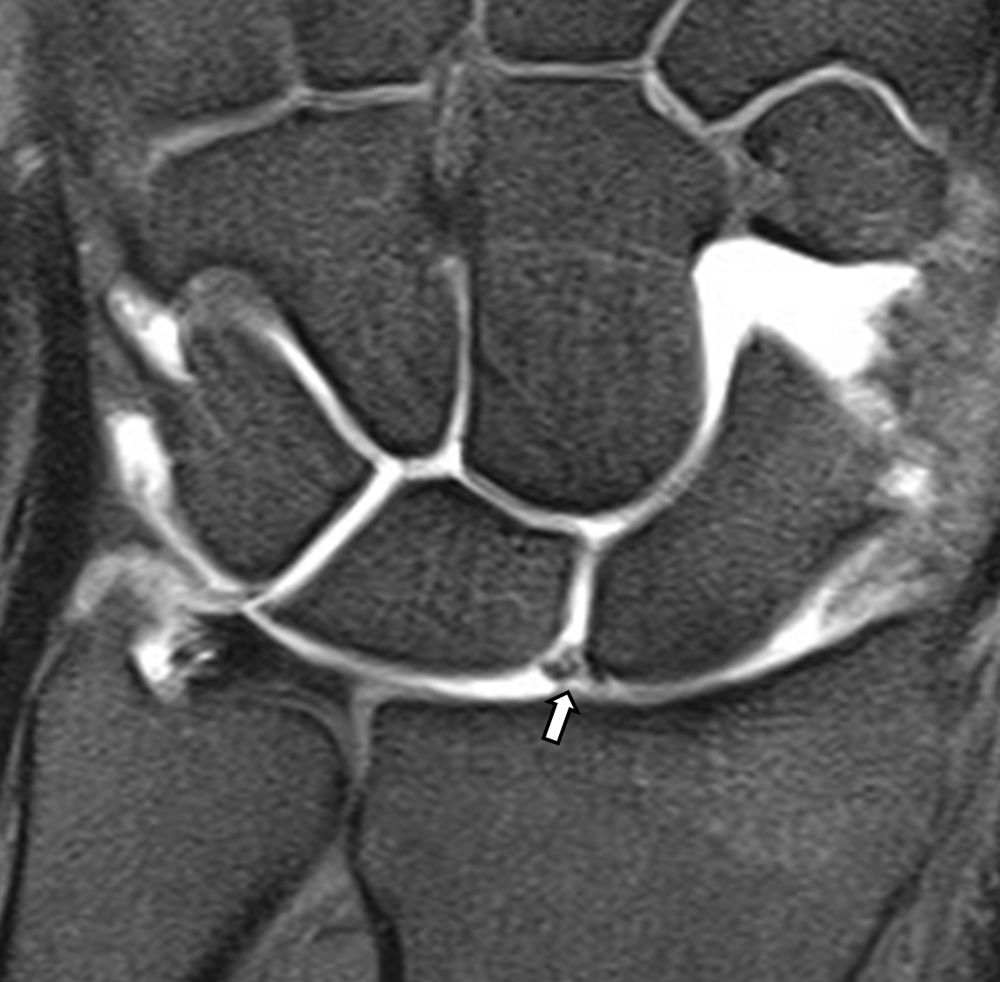

Είναι μια ελάχιστα επεμβατική απεικονιστική μέθοδος που επιτρέπει τη λεπτομερέστερη διερεύνηση του εσωτερικού των αρθρώσεων. Η ασφαλής έγχυση σκιαγραφικού εντός της άρθρωσης υπό ακτινολογική καθοδήγηση και η ακόλουθη απεικόνιση της άρθρωσης με αξονική ή μαγνητική τομογραφία (ή και με συνδυασμό των μεθόδων) αποσαφηνίζει βλάβες του χόνδρου και κακώσεις-ρήξεις συνδέσμων και τενόντων με υψηλή ακρίβεια, συμβάλλοντας σημαντικά στο λεπτομερή χειρουργικό σχεδιασμό.